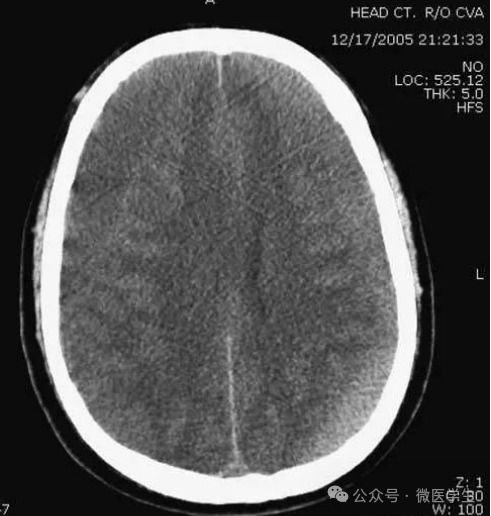

缺血性脑卒中

- 早期:脑水肿,灰白质分界模糊,脑沟消失;

- 中期:病变区域密度减低;

- 晚期:脑实质体积缩小。

A:陈旧性脑梗死,右枕叶体积缩小;

B:左枕叶急性脑梗死,灰白质分界模糊,脑沟消失;

另一患者:

C、D:亚急性期脑梗死,低密度,无明显占位效应。